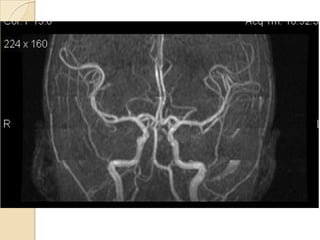

NORMAL MRA

Arteries of the brain (cranial view) - MRA

1. Anterior cerebral artery

2. Anterior communicating artery

3. Basilar artery

4. branches (in insula) of middle

cerebral artery

5. Cavernous portion of internal

carotid artery

6. Cervical portion of internal carotid

artery

7. Genu of middle cerebral artery

8. Intracranial (supraclinoid) internal

9. Middle cerebral artery

10. Ophthalmic artery

11. Petrous portion of internal carotid

12. Posterior cerebral artery

13. Posterior cerebral artery in ambient

cistern

14. posterior cerebral artery in

interpeduncular cistern

15. Posterior communicating artery

16. Posterior inf cerebellar artery.

17. Quadrigeminal portion of posterior

18. Superior cerebellar artery

19. Vertebral artery